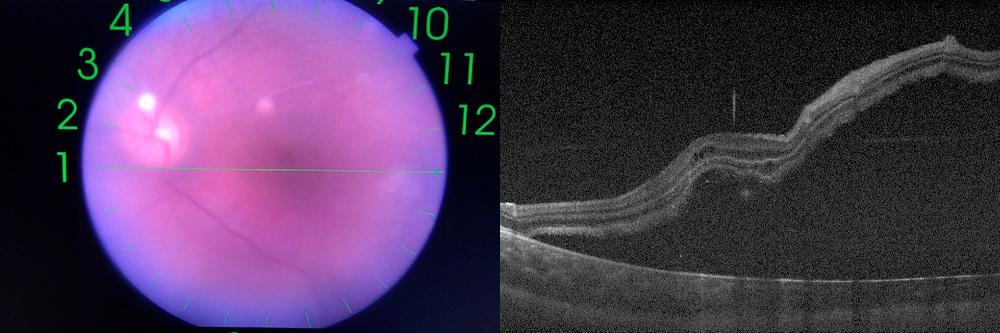

Se realizó interconsulta al servicio de Oftalmología, siendo diagnosticando de desprendimiento de retina crónico macula off (Fig. 1) secundario a desgarro retiniano gigante en región temporal inferior de OI. Se realizó vitrectomía, cerclaje escleral y aplicación de endoláser y aceite de silicona como endotamponador.

| Figura 1. Desprendimiento crónico de retina secundario a desgarro retiniano gigante en la región temporal inferior del ojo izquierdo |

Seis meses después de la segunda intervención, persiste AV 1/10 en OI, manteniendo la lente intraocular implantada y la retina reaplicada en polo posterior (Fig. 2). No se encontraron lesiones destacables en el ojo contralateral.